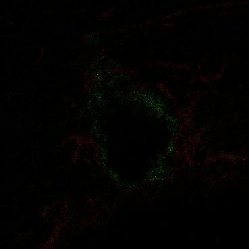

Finally, we applied our algorithm on a real confocal microscopy image of neurons. Fig. 4(a) depicts the observed image222Courtesy of the GIP Cycéron, Caen France. using the GFP fluorescent protein. Fig. 4(b) shows the restored image using our algorithm with the orthogonal wavelets. The images are shown in log-scale for visual purposes. We can notice that the background has been cleaned and some structures have reappeared. The spines are well restored and part of the dendritic tree is reconstructed, however some information can be lost (see tiny holes). This can be improved using more relevant transforms.